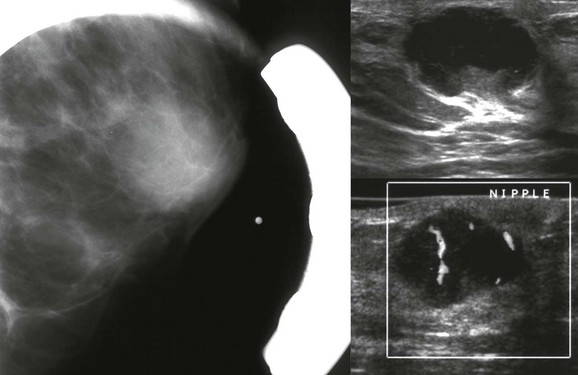

Papillary carcinoma represents 1% to 2% of breast cancers. Papillary carcinoma shares some similarities with benign papillomas. Both most commonly present as intraductal or intracystic masses (Fig. 11-9), may be associated with nipple discharge, and are frequently located in the subareolar region. Papillary carcinoma often presents as a palpable mass. On mammography, papillary carcinoma is usually a round or oval, circumscribed, equal- to high-density mass. On US, the most common finding is an intraductal or intracystic mass. These cancers are termed encapsulated (or intracystic) papillary carcinoma. Because the cancer is largely confined to the contents of the cyst, these lesions behave and are treated in a manner similar to DCIS. If the cancer invades through the wall of the cyst, the size and degree of invasion determine management and outcome. So, a woman with a 3-cm palpable intracystic papillary carcinoma may only have a 5-mm invasive component, and is treated and staged based on the 5-mm measurement. The prognosis for these tumors is excellent.

FIGURE 11-9 Intracystic Papillary Carcinoma.

This patient presented with a palpable lump that corresponds to an oval, circumscribed, high-density mass on mammography and a complex mass on US. At histologic examination, only a few millimeters of invasive tumor were present. (Reprinted with permission from Harvey JA. Unusual breast cancers: Useful clues to expanding the differential diagnosis. Radiology 2007;242:683-694.)